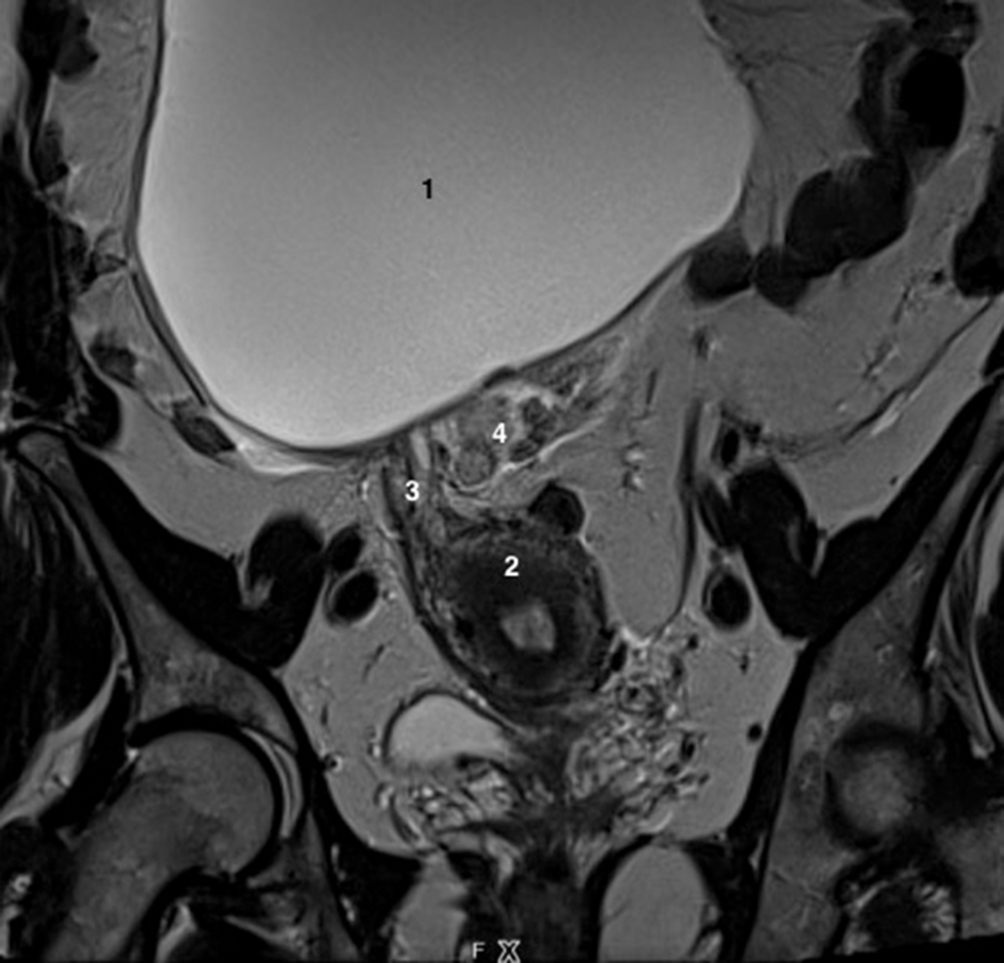

Fig. 20.8 IRM pelvienne. Patiente de 46 ans présentant des douleurs pelviennes latéralisées.

1. Pubis. 2. Vessie. 3. Fibrome sous-séreux corporéal latéralisé à gauche en franc hyposignal T2, en remaniement hyalin. 4. Rectum.

Source : CERF, CNEBMN, 2022.

L’IRM dynamique (figure 20.9) permet de faire le bilan complet d’un prolapsus complexe avant de décider de la chirurgie à proposer, et également de chercher une éventuelle cause anatomique à des anomalies d’évacuation ou de rétention du contenu intestinal.

Fig. 20.9 Patiente de 65 ans, présentant une boule vaginale à l’effort. Une IRM pelvienne est réalisée. La séquence rapide sagittale T2 retrouve une hystérocèle de grade III (H) et une cystocèle de grade III (C).Il n’existe pas de rectocèle.